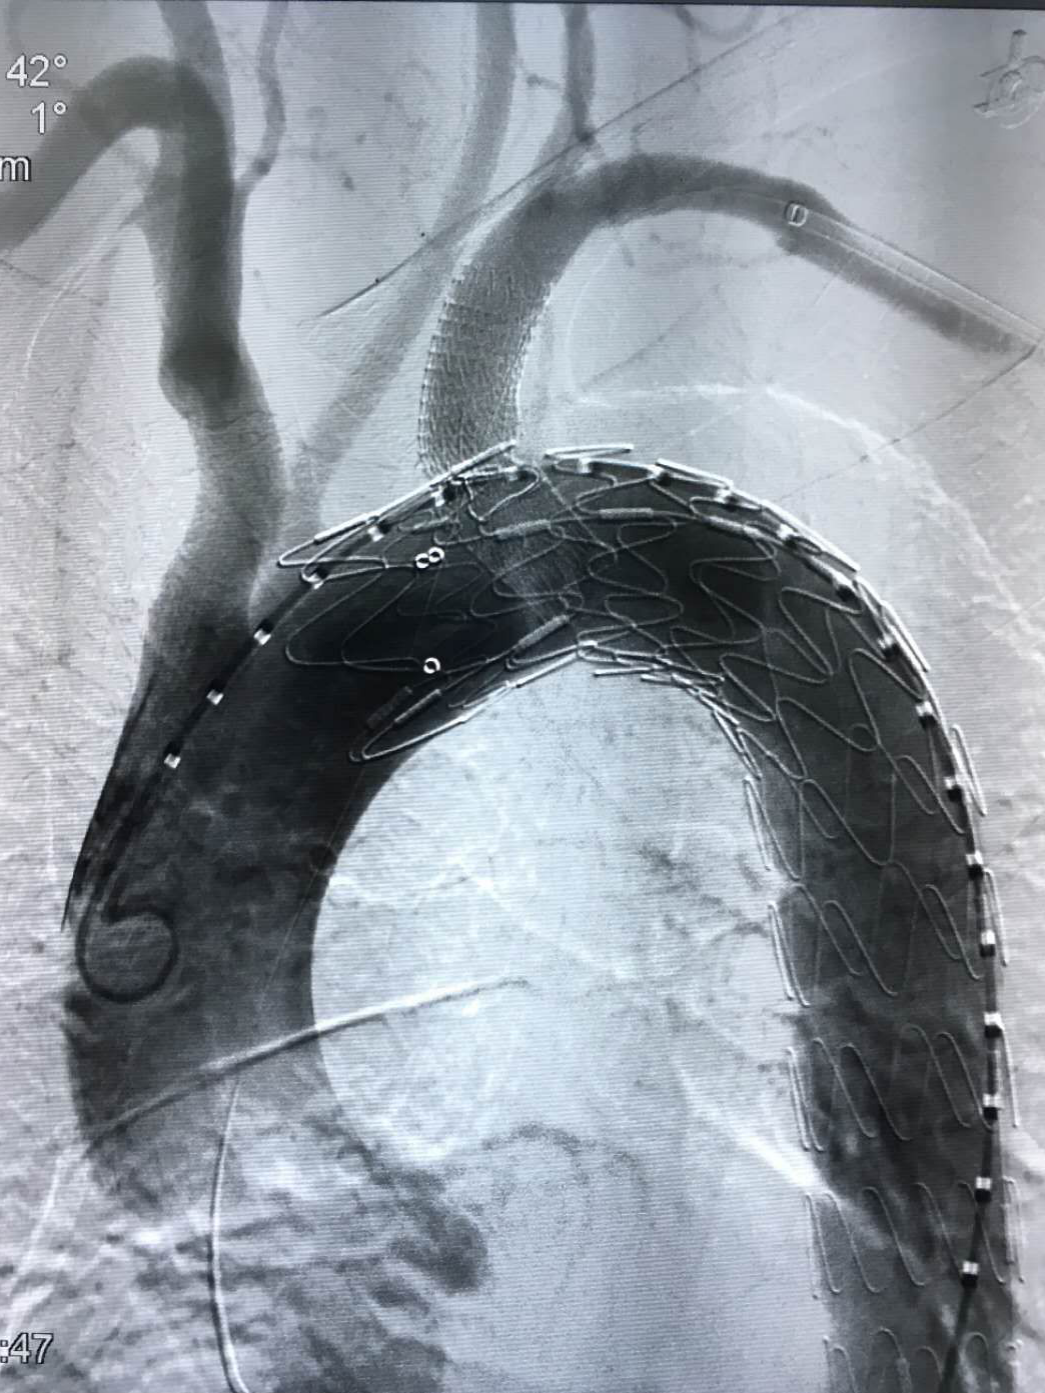

我院对新技术开展格外重视,全力支持新技术的开展。在易俊方主任的精心组织下,术前经过反复、严谨、精确的测量,积极做好术前准备,与患者充分沟通并取得患者的信任与配合。8月3号,我院介入血管外科在急诊科、急重症医学科、麻醉科、介入导管室等多科室协作下,经过3个小时的努力,手术进行顺利,术后造影效果满意。

8月3号,晋江市医院介入血管外科在急诊科、急重症医学科、麻醉科、介入导管室等多科室协作下,成功完成福建省县级市医院首例自主完成的“胸主动脉夹层腔内支架隔绝+体外开窗左锁骨下动脉分支支架植入”手术,有效防止主动脉夹层血管破裂致命性出血,为血管疾病患者保驾护航,标志着我院介入血管外科在大动脉疾病的腔内治疗方面踏上新的起点。